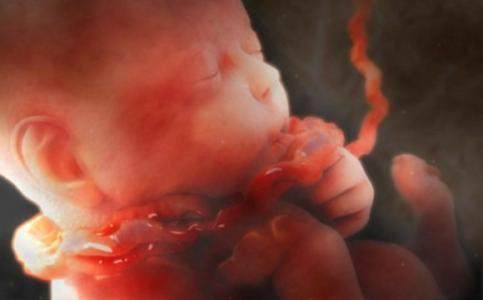

大多数情况是没有什么危害的,因为脐带不会缠绕的太紧,少数情况下,如果宝宝脐带缠绕过紧或脐带过短,在出生以前会出现缺氧,表现为胎心减速,医生会在胎心监护中发现这种情况。所以一定要做孕检哦~

如果是头部娩出时发现脐带缠绕的太紧了,这时候助产师会在胎儿将身体娩出之前,把脐带剪断,然后尽快的将宝宝分娩出。

有些脐带绕颈的产妇担心自己顺产时会出现危险,因而选择剖腹产。事实上,胎儿在分娩时脐带绕颈是一件很平常的事,并不一定需要剖腹产。若脐带绕颈不紧并有足够长度,产妇是可以顺产的。若绕颈圈数多且紧,脐带相对过短,胎头不下降或胎心明显异常,才需要考虑是否手术。